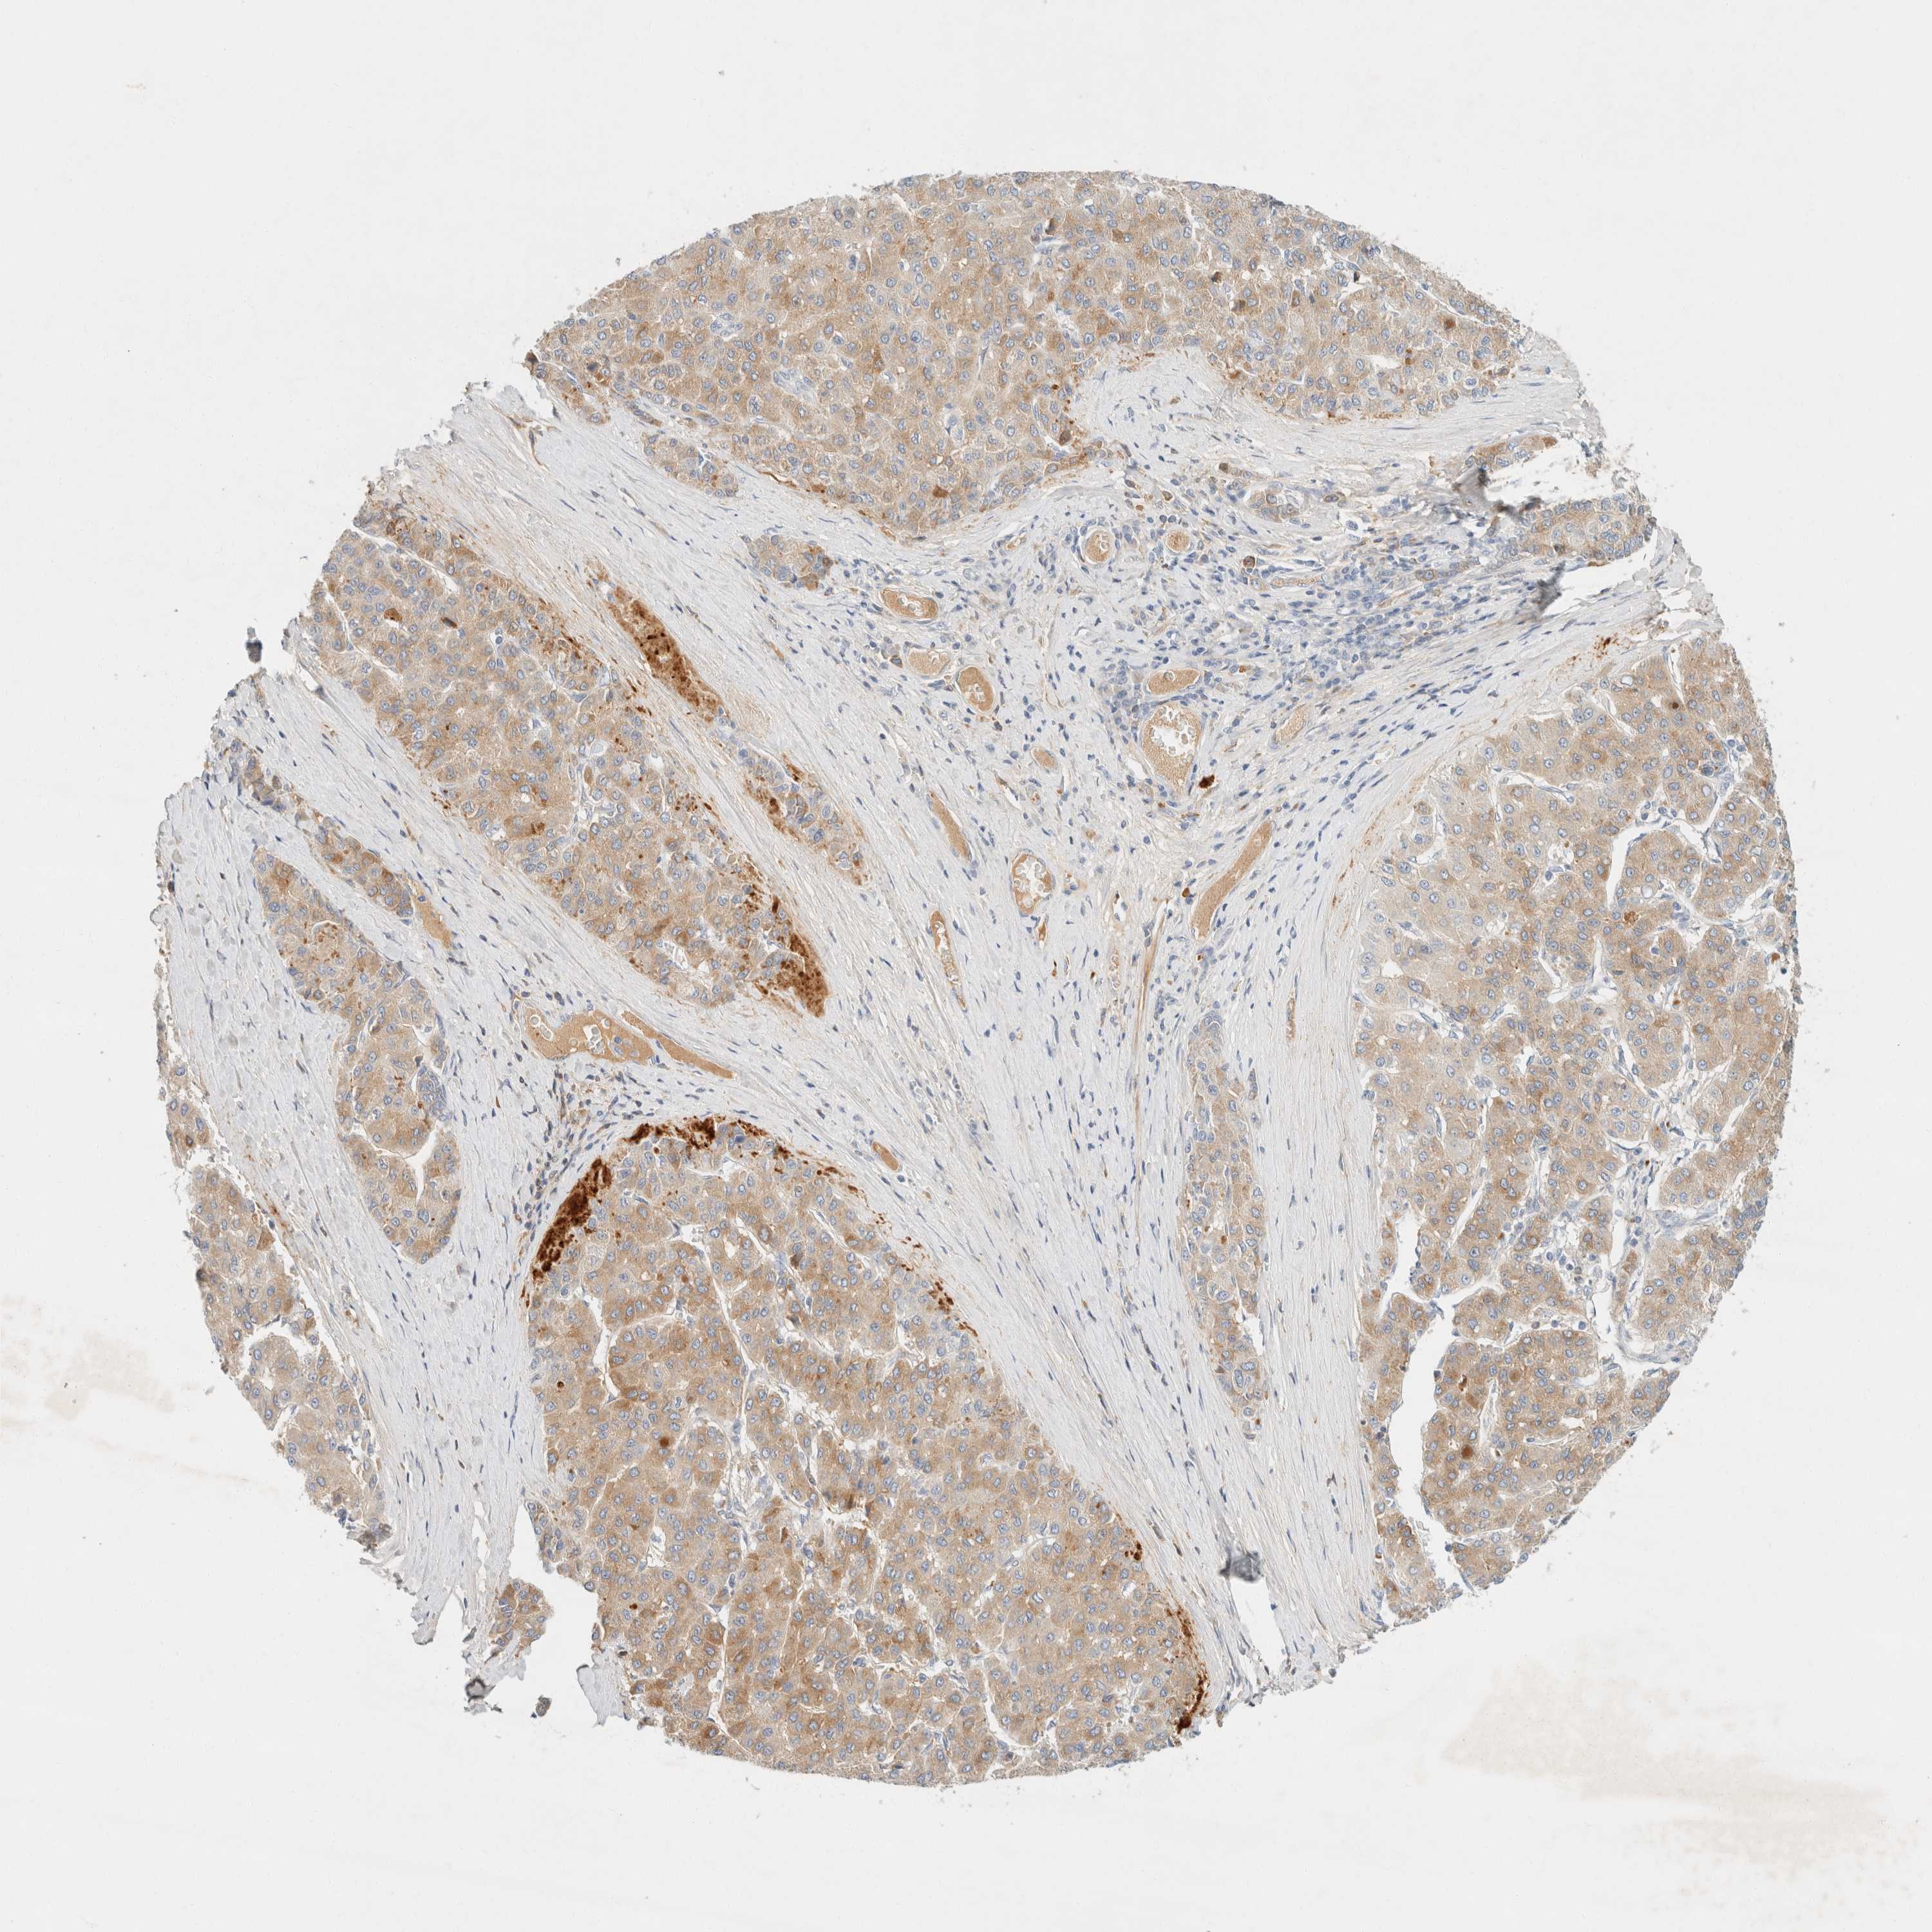

LIVER CANCER - Protein expressioni

A mouse-over function shows sample information and annotation data. Click on an image to view it in a full screen mode. Samples can be filtered based on level of antibody staining by selecting one or several of the following categories: high, medium, low and not detected. The assay and annotation is described here.

Note that samples used for immunohistochemistry by the Human Protein Atlas do not correspond to samples in the TCGA dataset.

Antibody stainingi

Antibody staining in the annotated cell types in the current human tissue is reported as not detected, low, medium, or high, based on conventional immunohistochemistry profiling in selected tissues. This score is based on the combination of the staining intensity and fraction of stained cells.

Each image is clickable and will lead to virtual microscopy that enables deeper exploration of all samples and also displays staining intensity scores, fraction scores and subcellular localization as well as patient and tissue information for each sample.

Antibody HPA023694

Staining

High

Medium

Low

Not detected

Intensity

Strong

Moderate

Weak

Negative

Quantity

>75%

75%-25%

<25%

None

Location

Nuclear

Cytoplasmic/membranous

Cytoplasmic/membranous,nuclear

Cholangiocarcinoma

Carcinoma, Hepatocellular, NOS